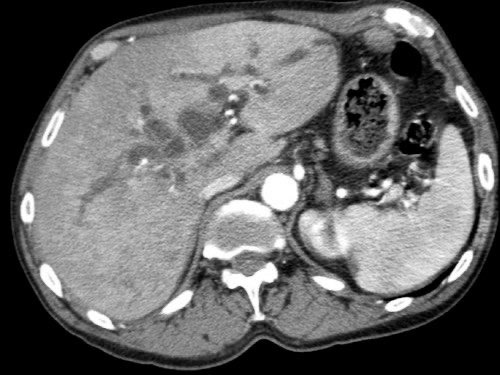

CT axial (a) trước điều trị tân bổ trợ cho thấy khối u ở mặt trong đầu tụy (đầu mũi tên), không thể cắt bỏ do xâm lấn thần kinh lan rộng với mức độ bao quanh 360 độ động mạch mạc treo tràng trên (SMA) (mũi tên trong b, tái tạo mặt phẳng coronal).

CT theo dõi sau 8 chu kỳ FOLFIRINOX (c,d) cho thấy bệnh ổn định với tình trạng bao quanh SMA vẫn còn tồn tại. Khối u được đánh giá có thể cắt bỏ trong quá trình phẫu thuật nội soi thăm dò. Kết quả giải phẫu bệnh: T3bN2R0.